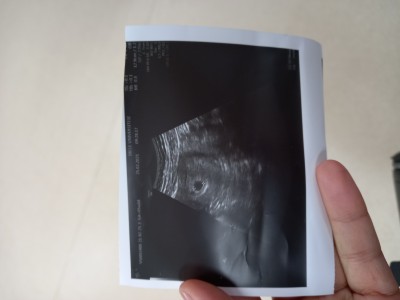

Kizlar burda adetime gore 5 hastalık ama doktor kese 6 haftalik görünüyor dedi ve 15 gun sonra kalp atışı için gel dedi içinde bebek var mi yada yok mu demedi sizce var mi anlamadım

image

Simdi gorunmez zaten canim sadece kesen gorunuz

Su an fotograftan gorunmuyor ama, ayni sey bende de oldu, 5 haftalikken gebe oldugumu ogrendim 7.haftada kalp atisini duydum. Ama ihtimaldir kese bos da olabilir tabi  her sey allahtan her ihtimale hazir sekilde ol canim allahim kalbine gore versin

Hayır sadece kese var 10 gün sonra bebekte görünür

6 haftalik daha kese oluşumunda bebek görünmez ilk önce kese sonra kalp sonra bebek

Kese kaç mm doktor söyledi mi ben de altıncı haftada duyamadım yarın kontrole gidicem 7+3 oluyoruz inşallah duyarız ikimiz de. Vajinal ultrasonda kese 22 mm olanakadar bebek görülmemesi normalmiş içiniz rahat olsun

Yok canim kese var sadece sonra kalp atisi sonrada bebis gozukur

Bebek gorunmuyor. ama bu gorunmeyecegi anlamina gelmiyor. Haftasi cok erken once kese olusur, sonra bebek gorunur.

Bebek yok canım yolk kesesi oluşmuş icinde yolk kesesi bebeğe dair ilk izlenimdir zaten haftaya gidersen bebegide görürsün